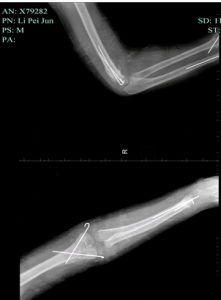

伸直型肱骨髁上骨折的特點是:骨折線位於肱骨下段鷹嘴窩水平或其上方,骨折的方向為前下至後上,骨折向前成角,遠折端向後移位。屈曲型肱骨髁上骨折的骨折線可為橫斷,骨折向後成角,遠折端向前移位或無明顯移位。

本病的輔助檢查方法主要是X線檢查:對患者使用X線檢查時,除正、側位X線攝片外,尚應根據傷情拍攝特殊體位相,尚應酌情行體層片或CT檢查。

3.影像學檢查

常規正、側位X線片即可確診及分型。